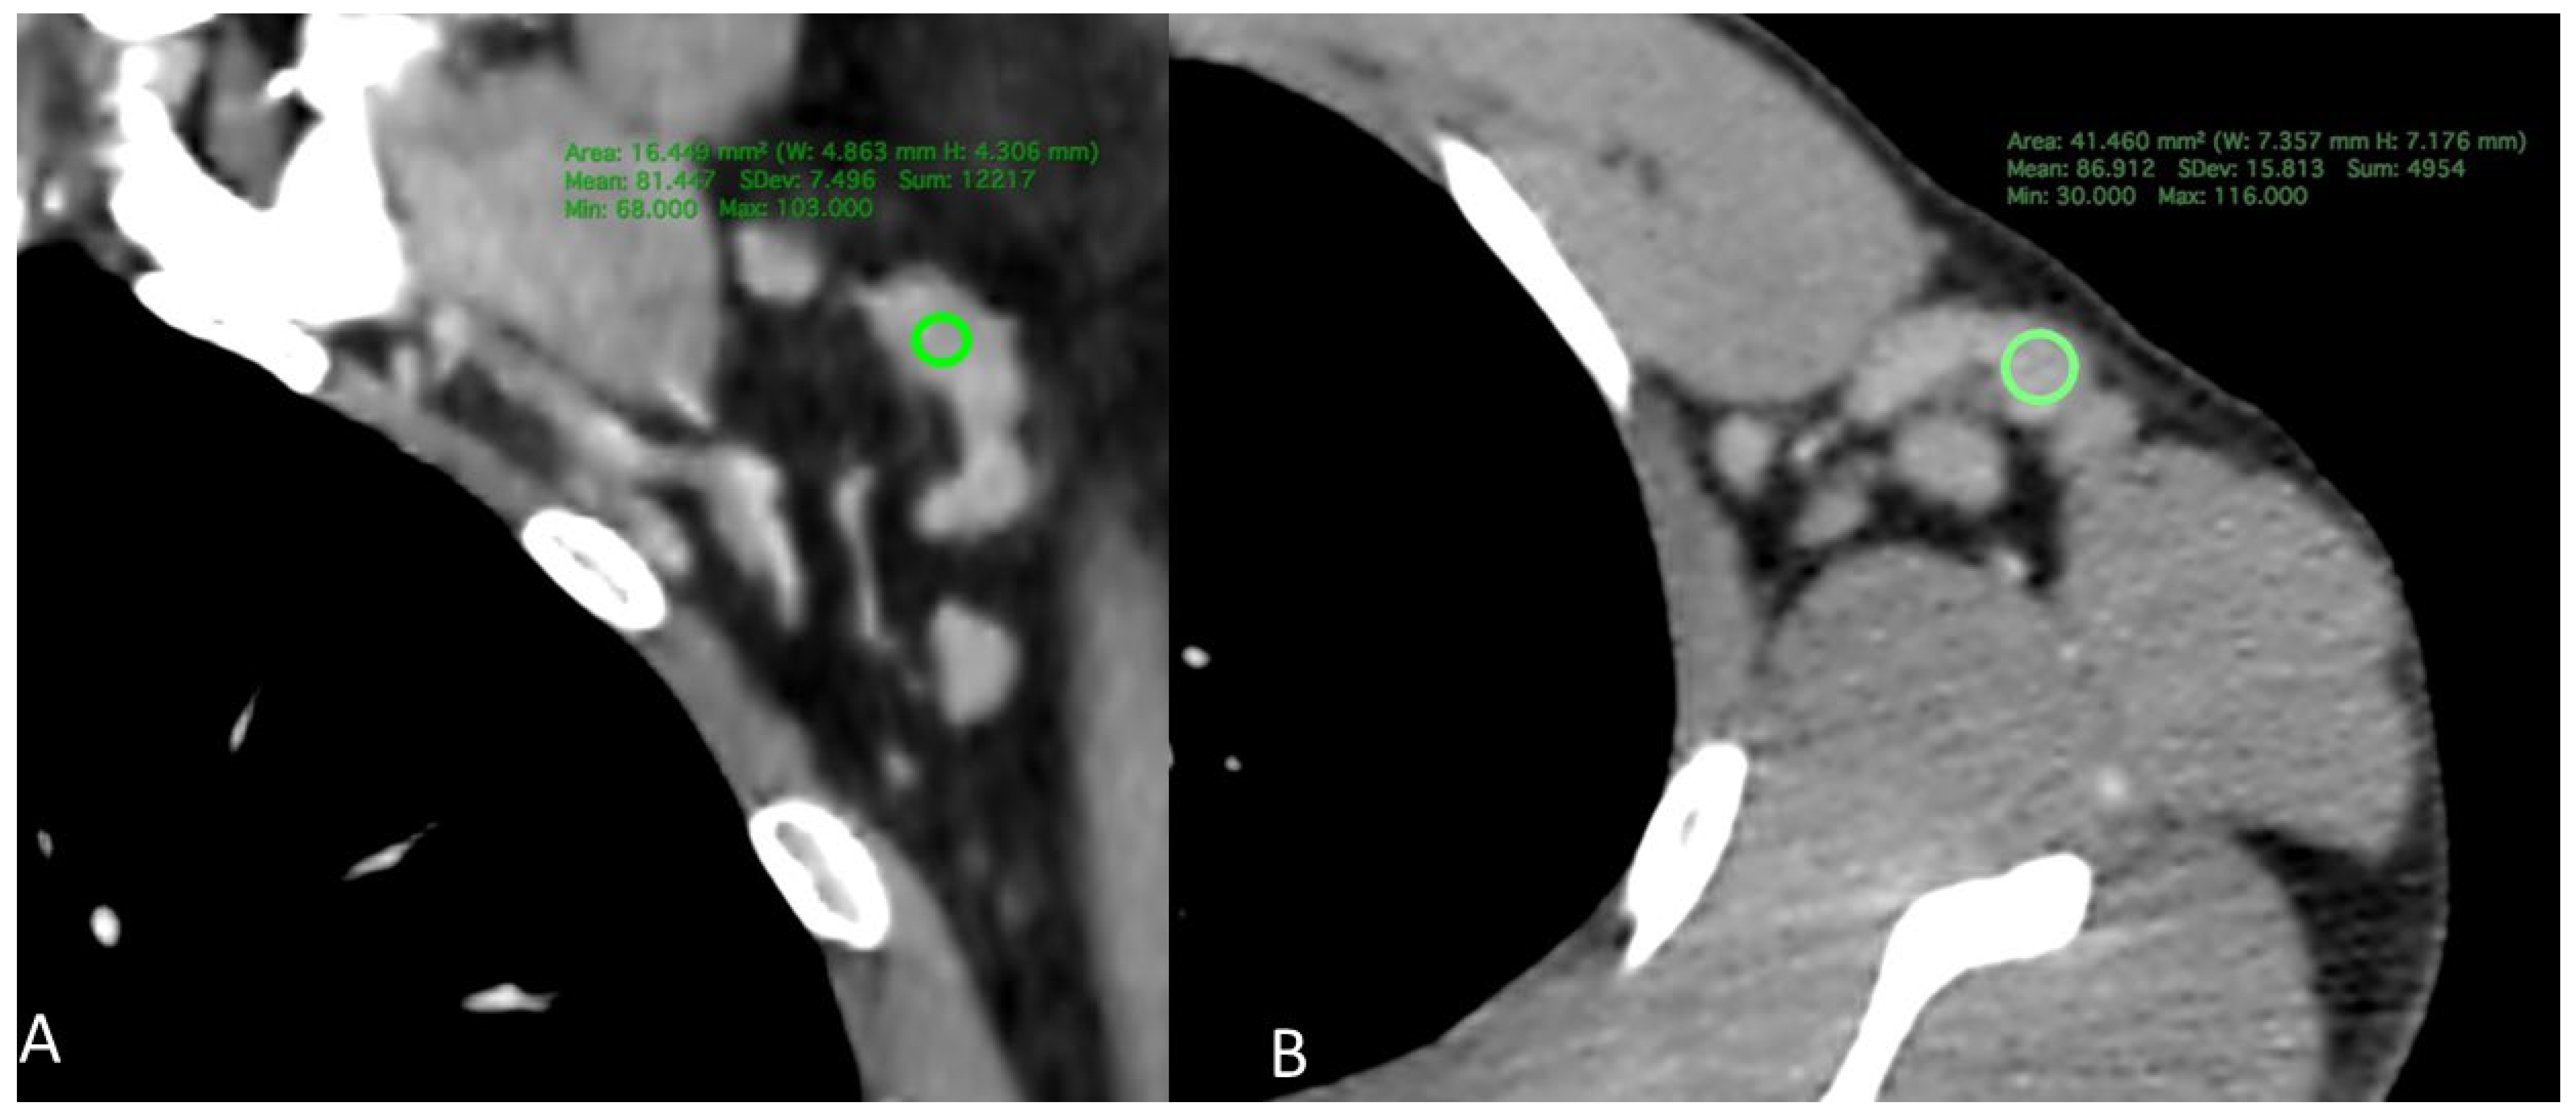

1.4. CT Measurement

2.4. CD4 Count and Density as a Predictor

2.5. Radiological Findings by Viral Load

3. Discussion